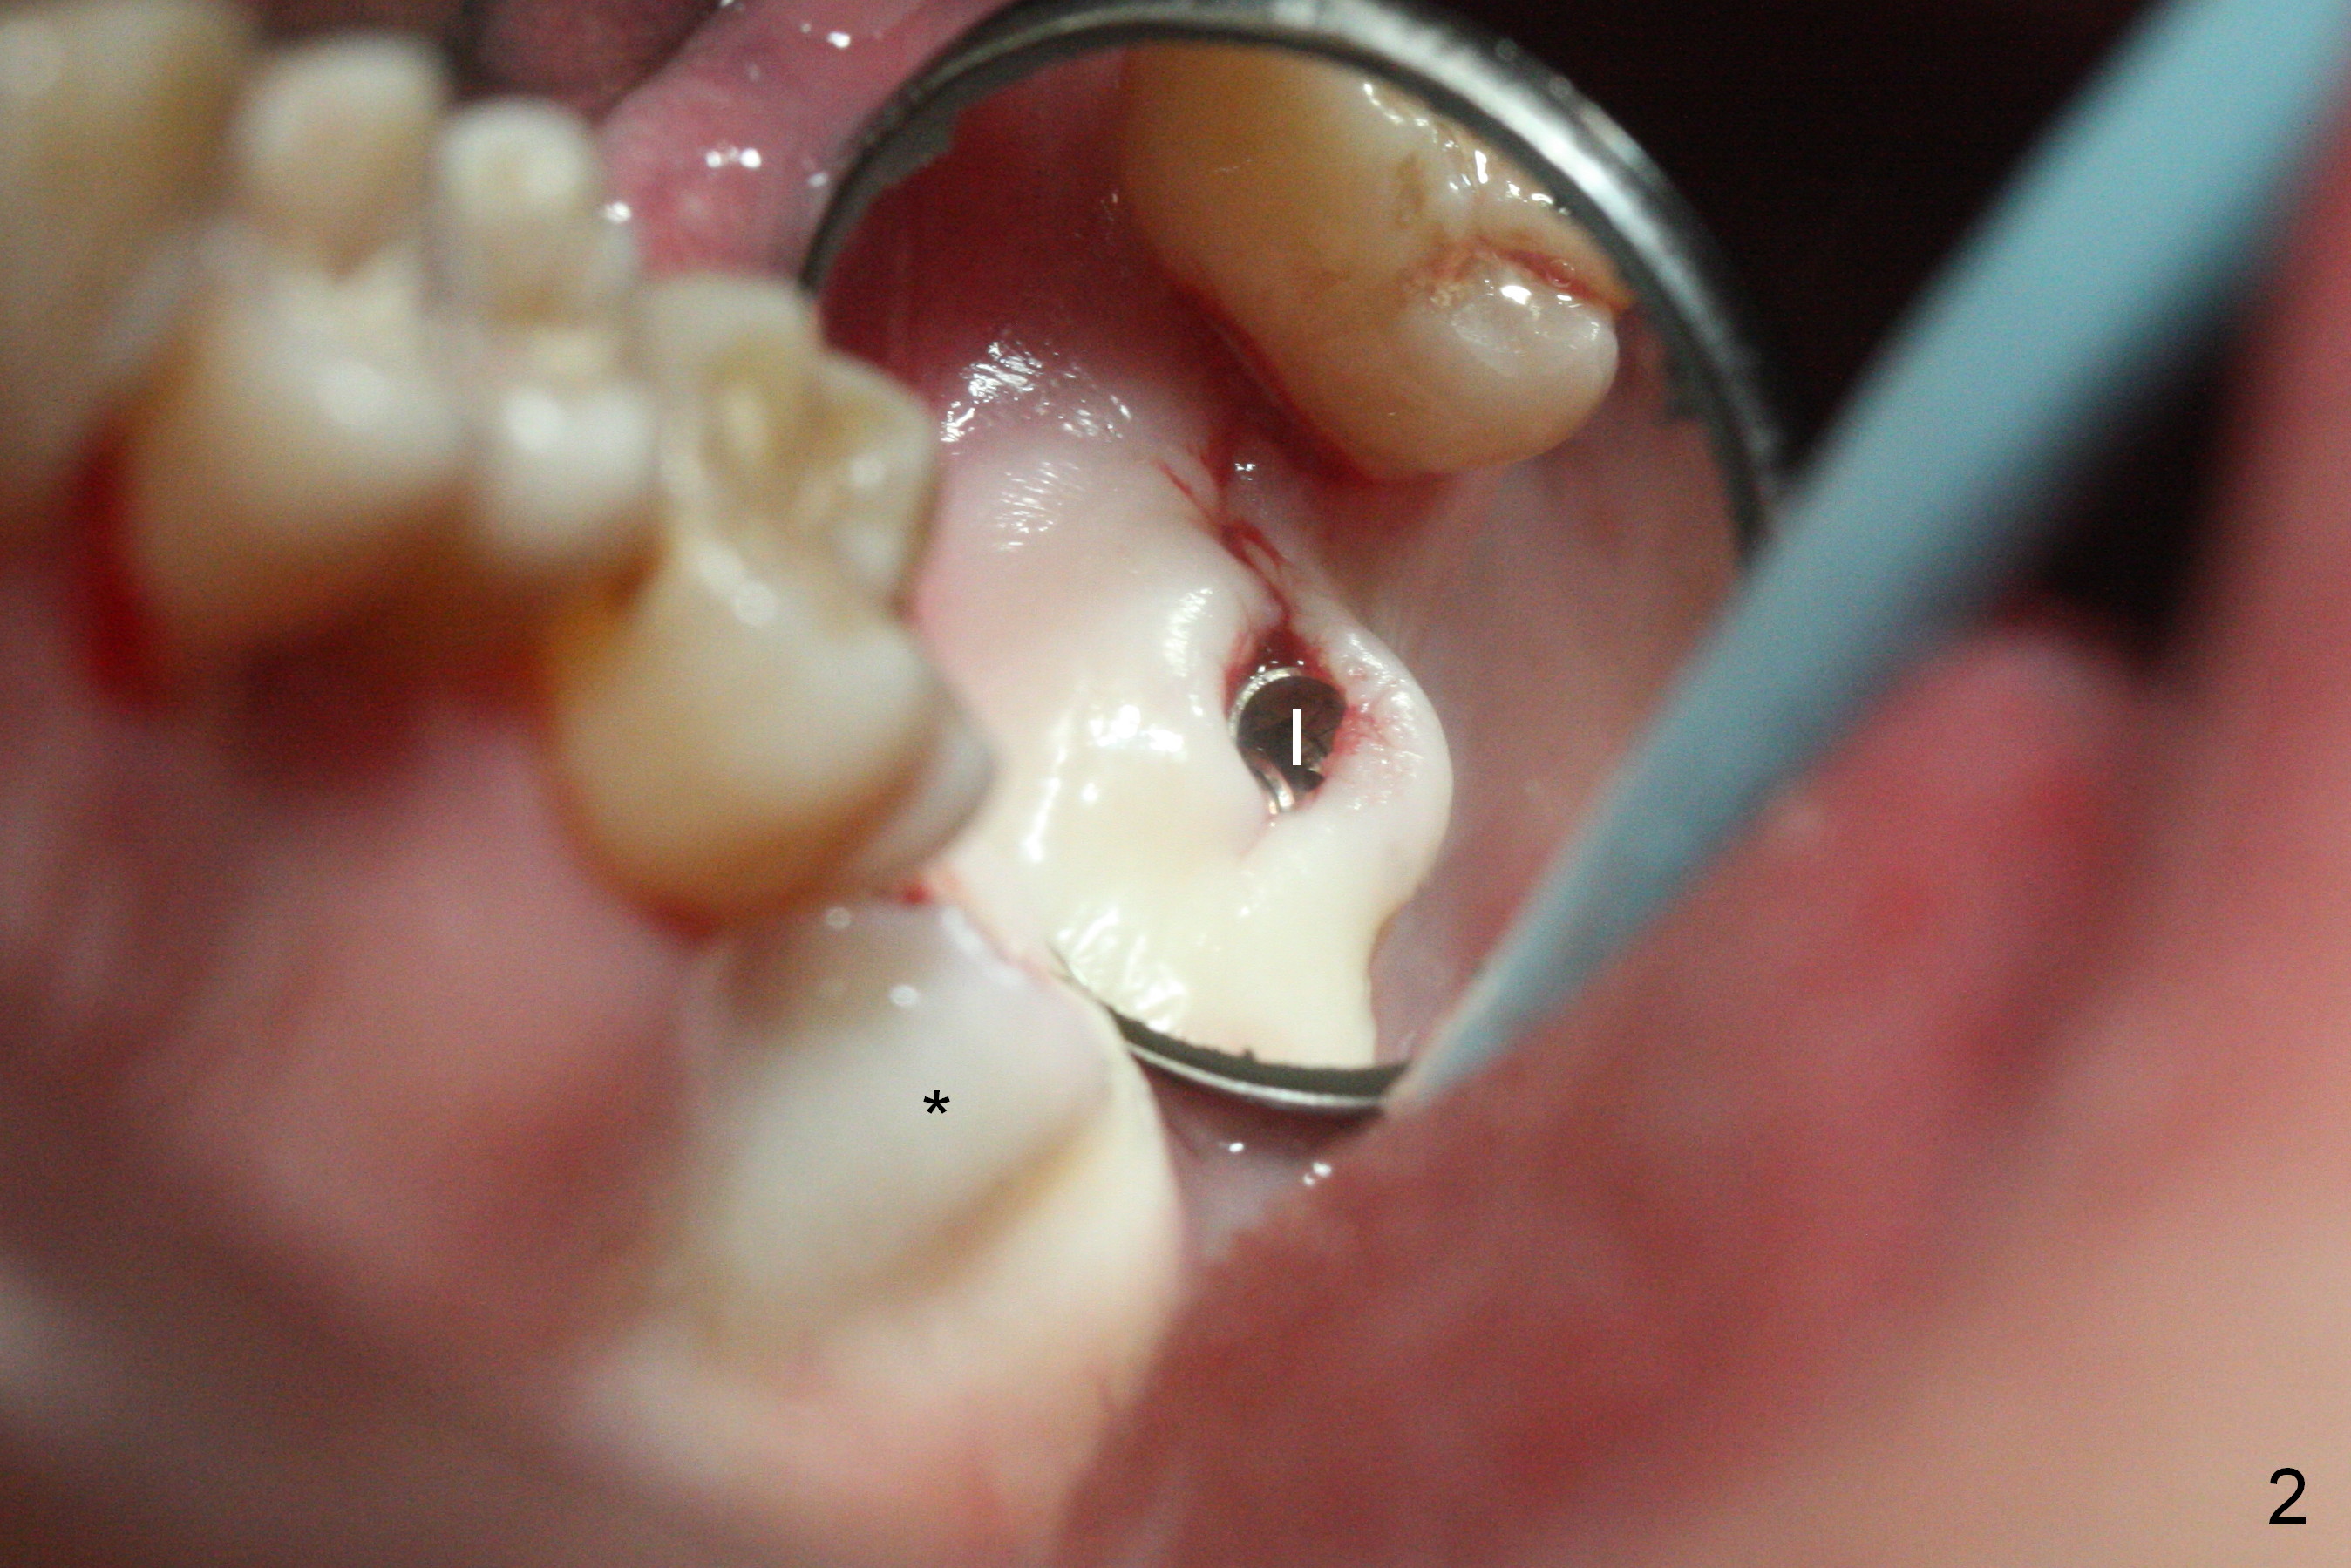

Initial osteotomy at the site of #15 for 4x11 mm dummy implant is created by #15 blade, Magic Split and Magic Expanders (ME) 3.0 and 3.8 mm (flapless, Fig.1,2, 4A (blue circle)). The implant is palatally displaced. Release incision confirms the deviation. A new osteotomy is established with 1.6 mm pilot drill in the middle of the site (Fig.4A (occlusal view) red circle). Distal to the new osteotomy is the incompletely healed socket (brown circle). As the osteotomy is enlarged by ME until 4.3 mm and placement of 4.5 and 5.0 mm dummy implant and of 5.5x9 mm definitive one (Fig.3, 4B large red circle), the osteotomy gradually deviates distopalatally. Introspectively, the new osteotomy should have been placed more buccomesially (Fig.4C red circle) so that the final osteotomy may end up normally (Fig.4D large red circle).

Prior to implant placement, two pieces of PRF plug are inserted. The insertion torque is <15 Ncm. A cover screw is placed. The distopalatal defect is covered by allograft and 1 piece of PRF membrane. There is no intraop sinus membrane perforation or nasal hemorrhage postop.